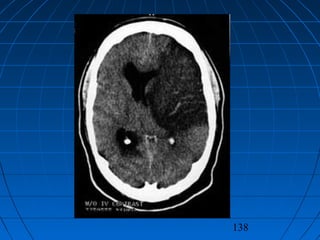

TIKAYICI SEREBROVASKÜLERTIKAYICI SEREBROVASKÜLER

HASTALIKLARHASTALIKLAR

NÖROŞİRURJİKAL YAKLAŞIMNÖROŞİRURJİKAL YAKLAŞIM

 Dekompressif kranyotomiDekompressif kranyotomi

 Karotid endarterektomiKarotid endarterektomi

 Ekstrakranyal - intrakranyalEkstrakranyal - intrakranyal

bypassbypass

137 TIKAYICI SEREBROVASKÜLERTIKAYICI SEREBROVASKÜLER HASTALIKLARHASTALIKLAR NÖROŞİRURJİKALYAKLAŞIMNÖROŞİRURJİKAL YAKLAŞIM  Dekompressif kranyotomiDekompressif kranyotomi  Karotid endarterektomiKarotid endarterektomi  Ekstrakranyal - intrakranyalEkstrakranyal - intrakranyal bypassbypass

• 138.